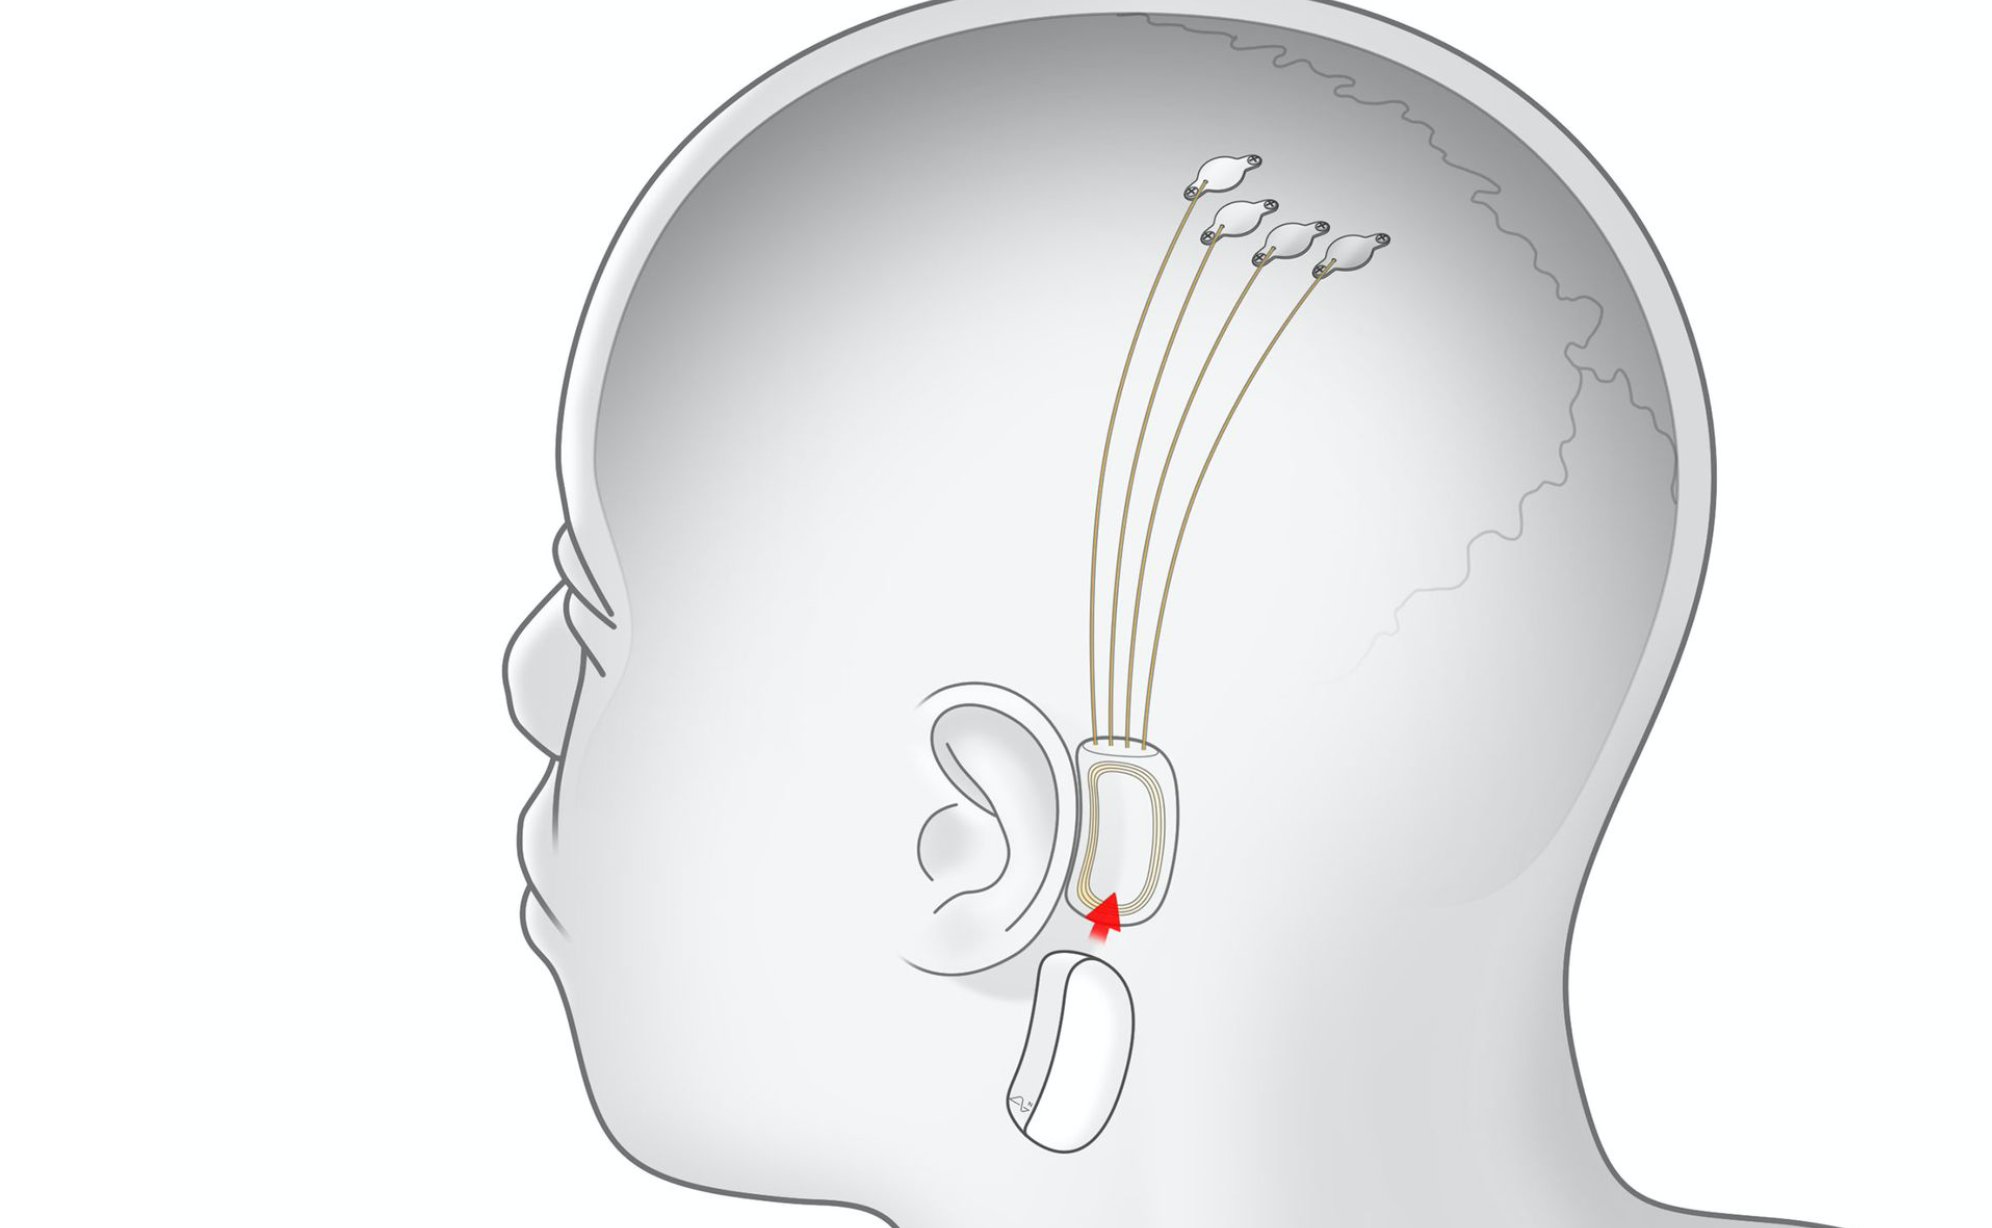

Ilon Masktiń Neuralink jobasy jip ımplanttaryn usyndy

Ilon Masktiń Neuralink jobasy mıǵa qaýipsiz chıpter ornatatyn tehnologııany tanystyrdy.